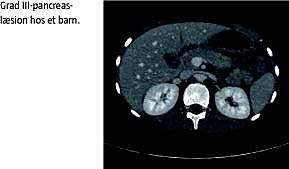

Pancreastraumer kan graderes efter sværhedsgrad, hvilket har betydning for prognosen og behandlingen [8]. American Association for the Surgery of Trauma (AAST) inddeler pancreastraumer i fem grader (I-V). Grad I-II betegnes som lette læsioner og er uden læsion af ductus pancreaticus, hvorimod grad III-V betegnes som svære læsioner med læsion af ductus pancreaticus (Tabel 1 ).